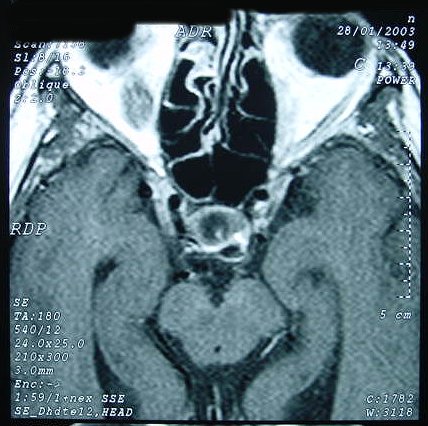

ГМ. Кавернома 2. Кавернома зрительного тракта. +

Кавернома зрительного тракта

Отдел патологии, школа медицинских наук. Государственного Университета Кампинас (UNICAMP). Кампинас, Сан-Паулу, Бразилия.